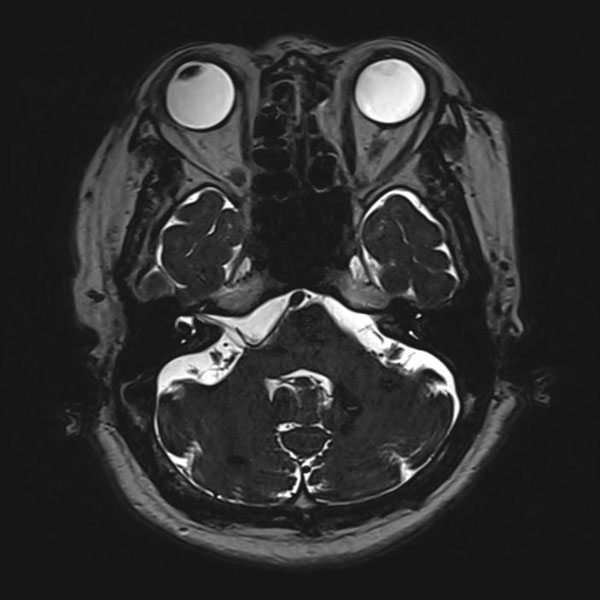

手術前

(MR1)